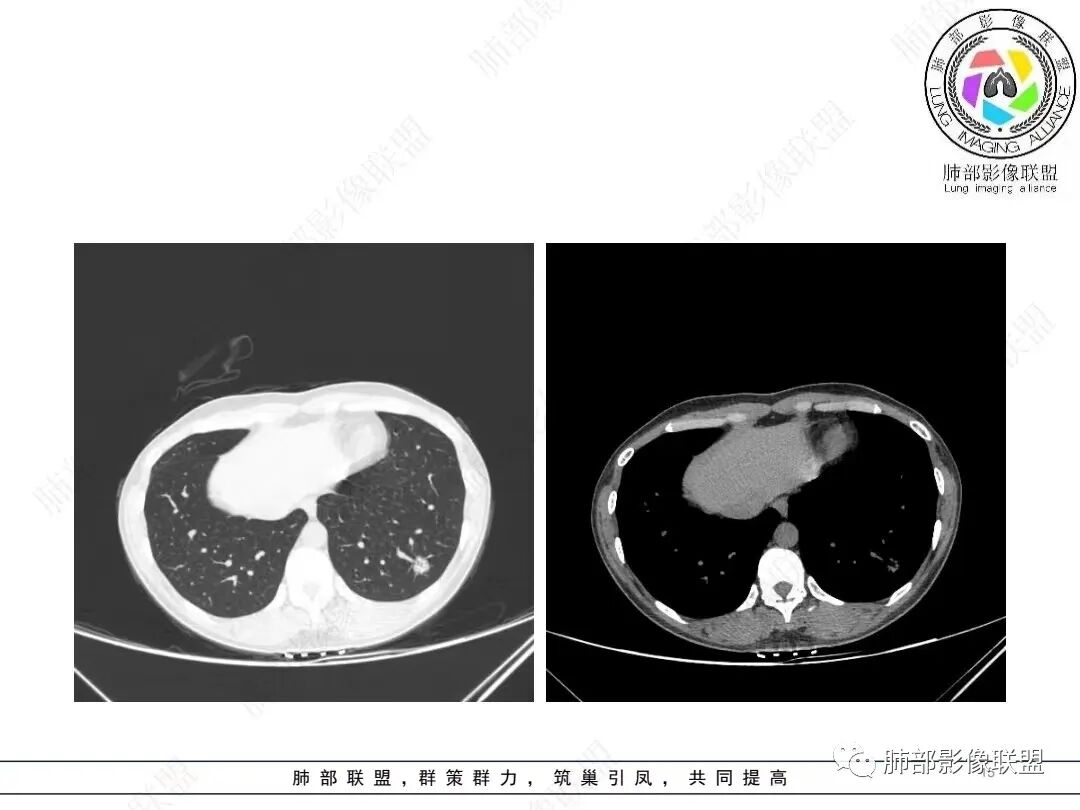

1、临床特点: 37岁女性,体检发现肺结节,2年前有甲状腺腺瘤手术史。实验室无阳性发现。

2、影像特点:左肺下叶类圆形结节影,周围可见多发细小毛刺,浅分叶,张力不高,未见胸膜牵拉。病灶内隐约见空泡影(未提供CT值),近端部分血管呈杵状增粗,可疑脐凹征。增强后实性部分有轻度强化。外围病灶,与支气管关系不明确。

4、病例小结:中青年女性偶然发现结节,表面欠光整,内部空泡,不均匀强化,边缘分叶毛刺等都具有影像学上的恶性征象,正如大多数老师所分析与肺腺癌较为符合。部分肺部肿瘤年轻化,尤其是肺腺癌等应当引发我们高度关注。